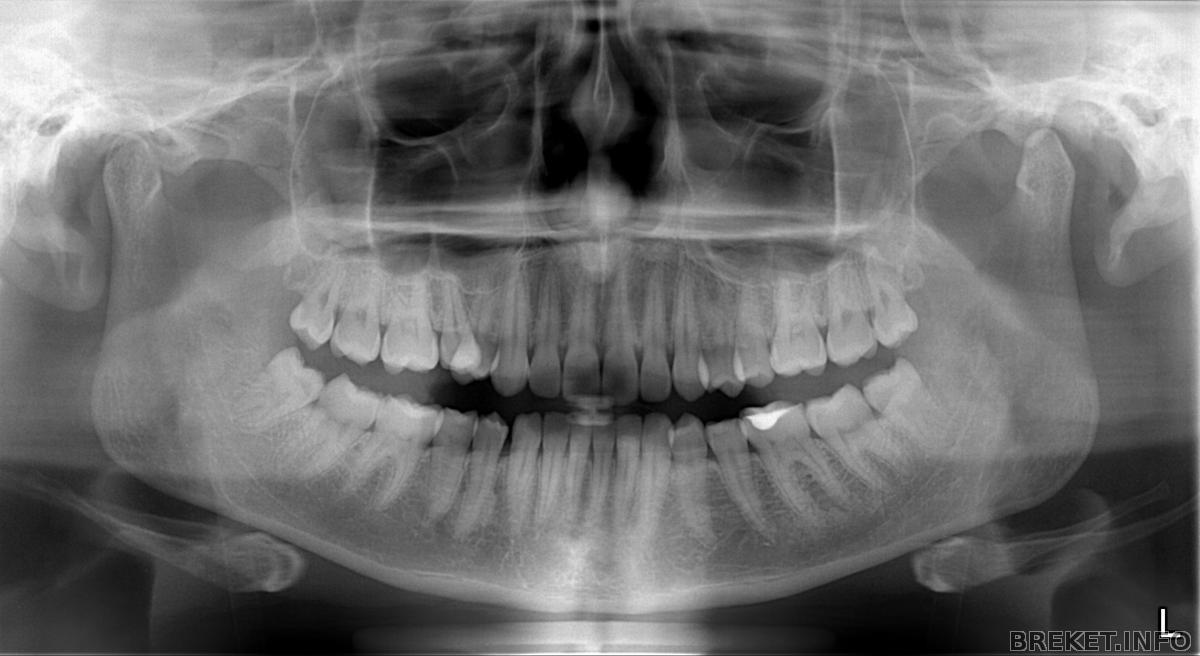

ОРТОПАНТОМОГРАММА (ОПТГ) — Панорамный рентгеновский снимок зубных рядов. Позволяет судить о состоянии всех зубов, наличии зачатков еще не прорезавшихся зубов, окружающих их костных тканях, височнонижнечелюстных суставов, гайморовых пазух.